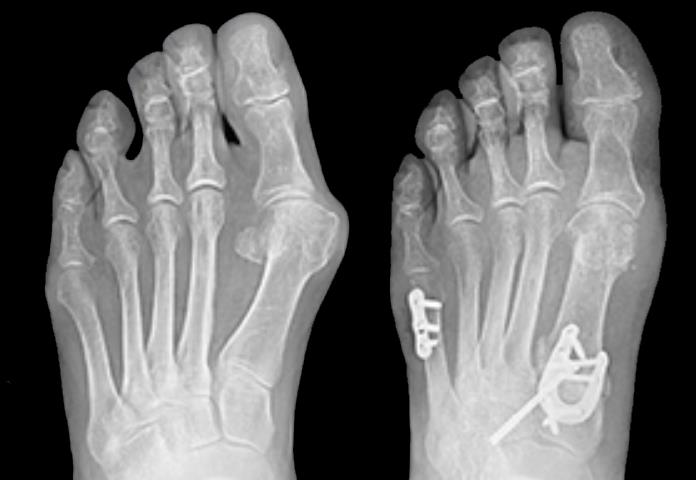

• LapiLock 4D Advanced Bunion Correction is described in manufacturer materials as a non-powered orthopedic manual bone positioner and jig system used for Lapidus bunion correction at the first tarsometatarsal joint, focusing on realigning and fusing the first metatarsal–medial cuneiform articulation rather than simply shaving the medial eminence.

• By shifting the correction proximally and addressing rotation, intermetatarsal divergence, and sagittal plane malalignment at the first tarsometatarsal joint, the system is intended to achieve a more anatomic and stable first-ray alignment than procedures that focus only on distal metatarsal osteotomy.

• Hallux valgus deformity commonly features an increased intermetatarsal angle between the first and second metatarsals, pronation of the first metatarsal around its longitudinal axis, and relative elevation or dorsiflexion of the first ray, with the sesamoid complex drifting lateral to the crista.

• Correcting at the first tarsometatarsal joint allows reduction of the intermetatarsal angle, restoration of sesamoid position under the metatarsal head, and re-establishment of a stable medial column, which can be more biomechanically advantageous than correcting only at the distal first metatarsal.